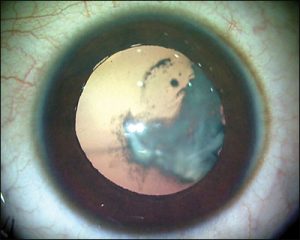

چه زمانی باید آب مروارید را عمل کرد؟

بسیار افراد با بالا رفتن سن به آب مروارید مبتلا می شوند و این سؤال پیش می آید که چه زمانی باید آب مروارید را عمل کرد؟ زمان مناسب جراحی آب مروارید چه زمانی است؟